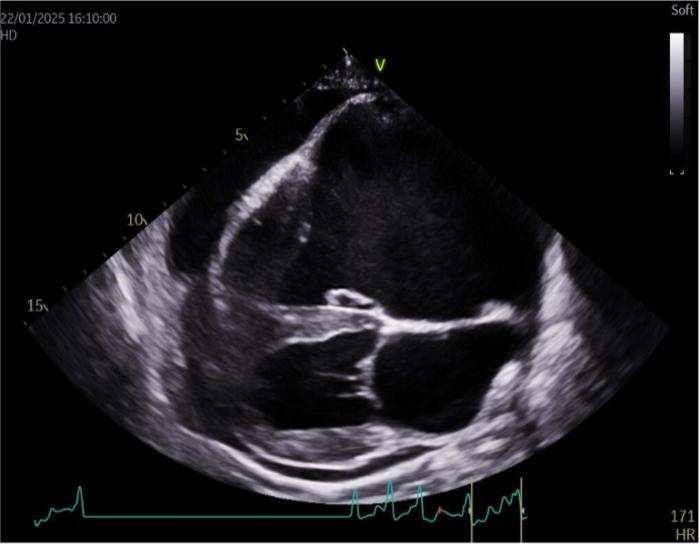

El examen ecocardiográfico muestra dilatación muy marcada del corazón derecho, con aplanamiento de los septos interauricular e interventricular. Además, el corazón izquierdo se muestra comprimido debido al agrandamiento del corazón derecho (Figura 3A-B). Durante el examen, se detecta displasia de la válvula tricúspidea, con una velocidad de regurgitación tricúspidea (RT) de 3.2 m/s (referencia <3 m/s), y mostrando la válvula una morfología engrosada y retraída. Además, la válvula mitral presentaba un engrosamiento leve.

Figura 3. (A) Corte paraesternal derecho de cuatro cámaras en el que se aprecia la dilatación marcada de las cámaras cardíacas derechas y la presencia de derrame pericárdico. (B) Eje corte por a nivel de base cardíaca, este corte se realiza por ventana paraesternal derecha con un eje transversal. En esta imagen se puede apreciar la dilatación marcada de la aurícula derecha.

En el examen por Doppler color, se detecta flujo turbulento severo a nivel de la válvula tricúspide (Figura 4A) y moderado en la válvula mitral. A nivel de la válvula pulmonar se detecta una leve insuficiencia, aunque muestra una apariencia normal. Las velocidades aórticas se encuentran por encima del límite normal, con un valor de 2.23 m/s (referencia: <2 m/s). La función sistólica se encuentra disminuida, con una fracción de acortamiento (FA) del 13.77 % (referencia: 28-45 %) y una fracción de eyección (FE) del 29.34 % (referencia: 40-75 %) (Figura 4B).

Durante el examen también se detecta la presencia de derrame pericárdico leve (ver Figuras 3A-B y 4A-B) sin evidencia de taponamiento cardíaco. El ECG durante el estudio ecocardiográfico confirma la presencia de fibrilación atrial.